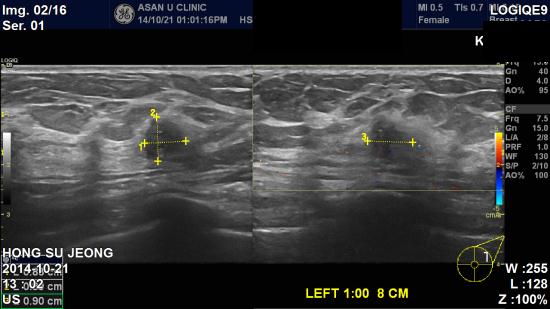

아산유외과 개원 후 162번째 유방암 진단.

2014.10월에 실시한 건강검진상 좌측 이상소견으로 내원하신

44세 여성분이십니다.

본원 초음파상 좌측 1시방향 젖꼭지 방향으로 8cm 떨어진 방향으로,

0.90cm 의 불분명한 결절이 발견 되었고,

조직검사 결과 상 좌측 침윤성 유관암으로 진단 되었습니다.

자가검진과 정기적인 검사로 건강하고 행복한 삶을 살 수 있기를 기원합니다.